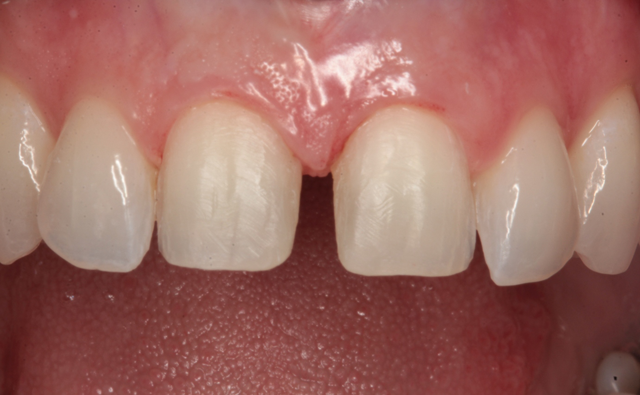

A preoperative impression was taken using Silginat alginate alternative impression material by Kettenbach. The previous laminates were carefully removed using a fine diamond bur (Brasseler) in a high speed handpiece with water spray. The prepared teeth can be seen from the facial view in Figure 4. The incisal view of the prepared teeth is shown in Figure 5. All prepared surfaces were in enamel.

Fig. 4 Fig. 5